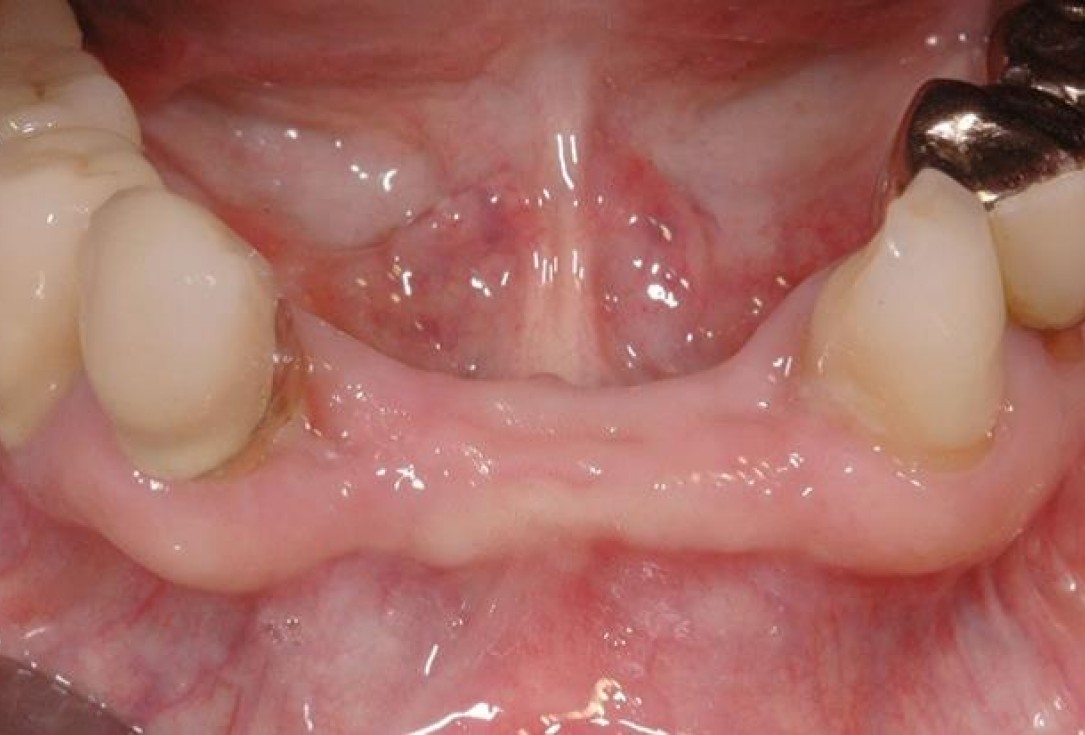

2/15 - 3 months after extraction visible bone and soft tissue loss in regio 42-32Soft tissue augmentation and GBR with mucoderm® and maxresorb® - Dr. S. Scherg